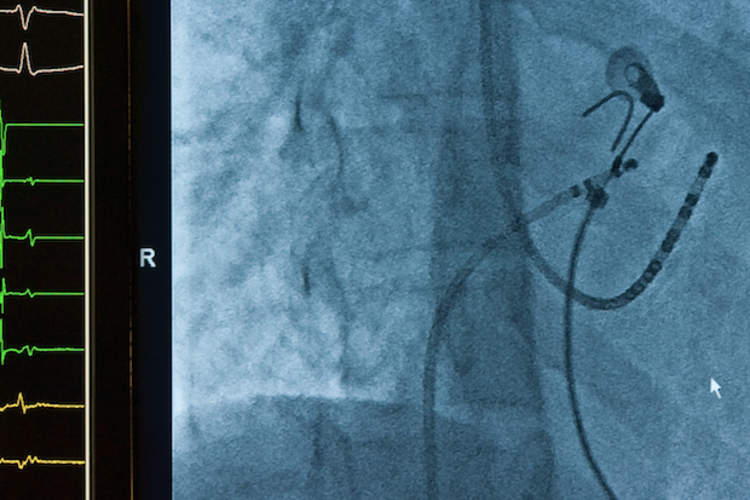

混合消融术治疗顽固AFIB

这个过程结合了两种方法来恢复正常的心脏节律,但它是否适合你?